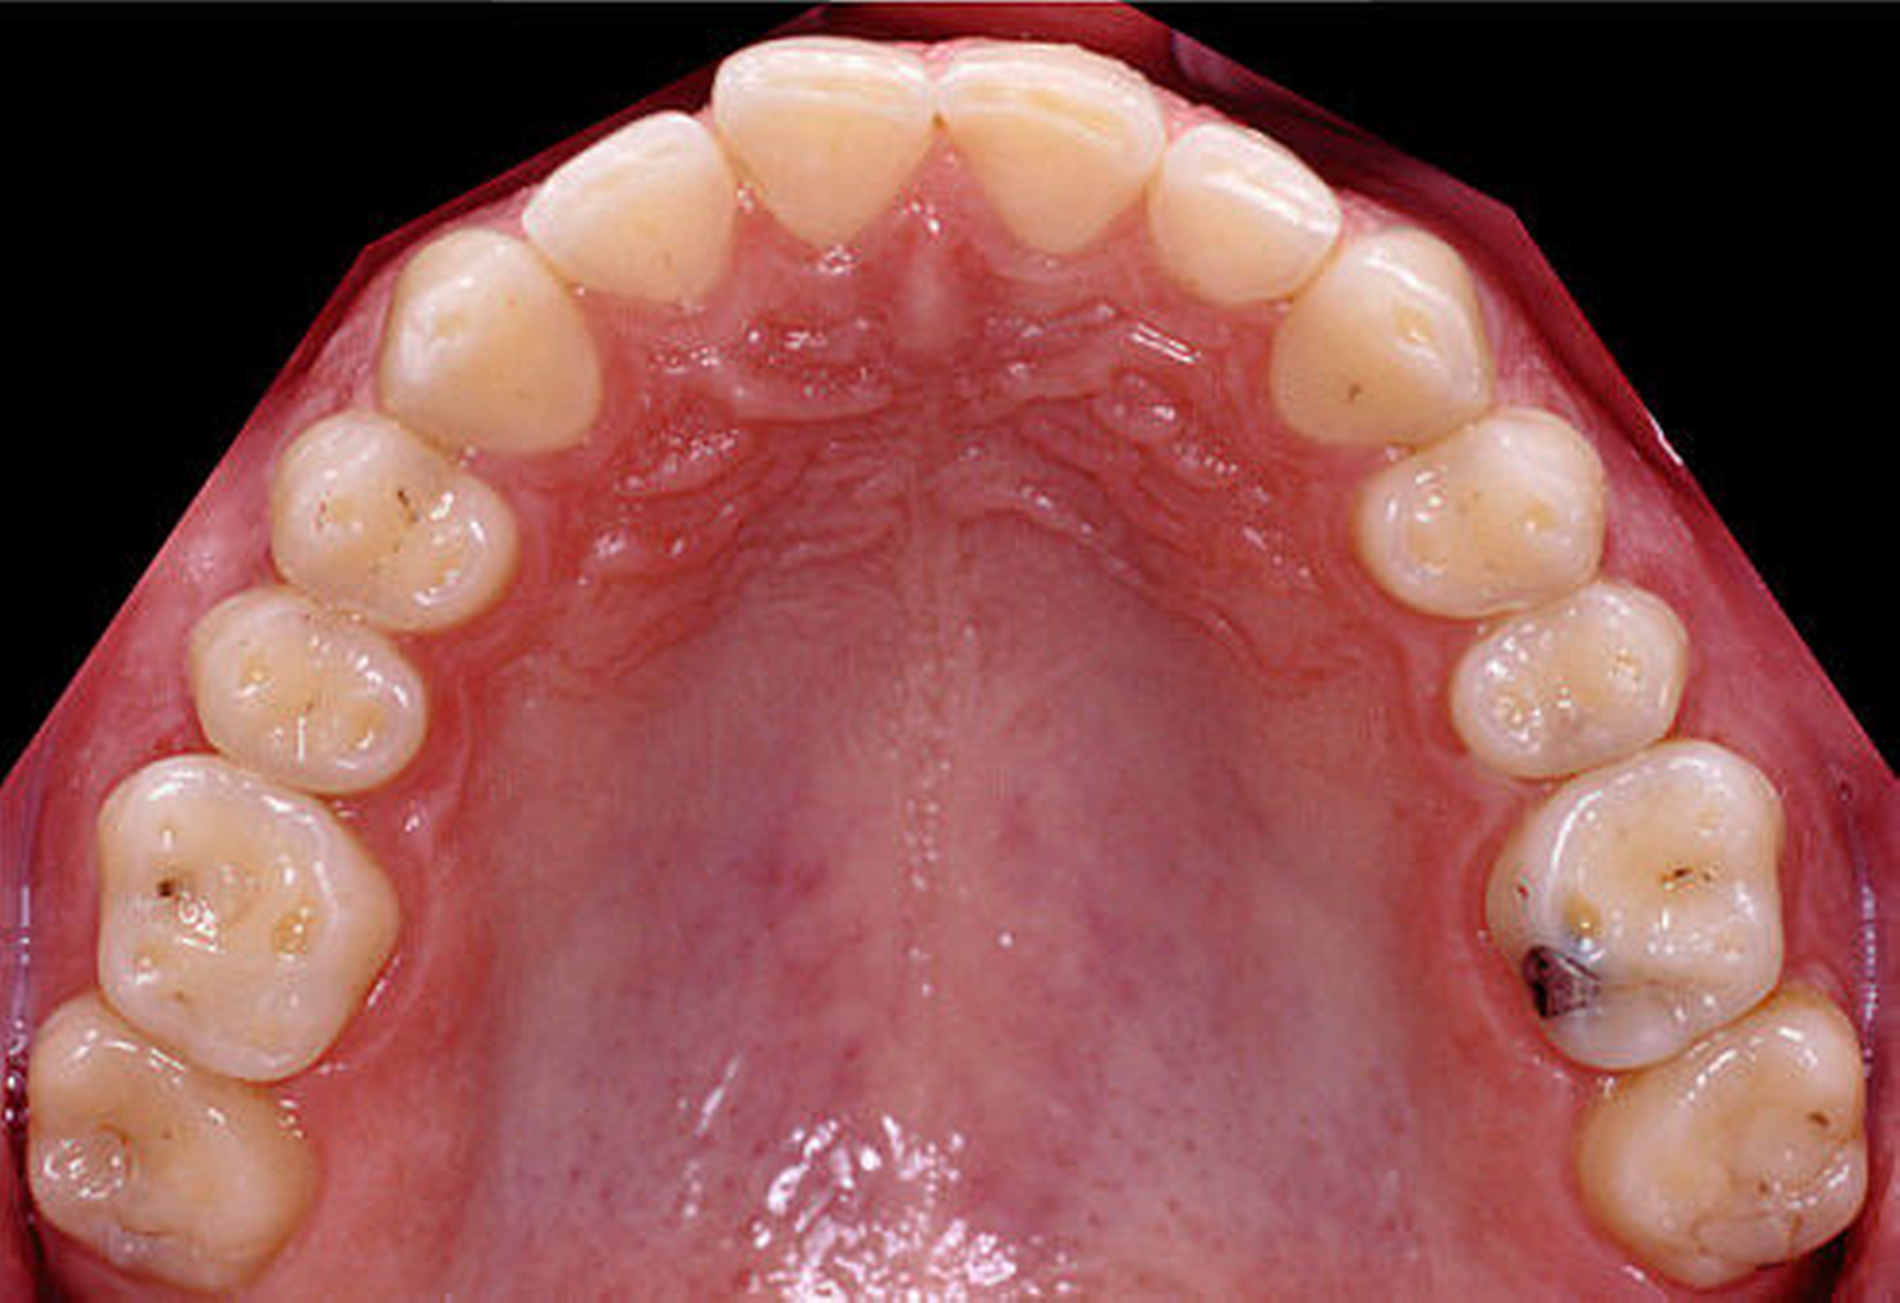

Auch Magensäure kann Zahnschäden verursachen, wenn sie häufig auf die Zähne einwirkt. Das kann beispielsweise der Fall sein bei Magenerkrankungen mit Reflux (wie Sodbrennen) und bei regelmäßigem Erbrechen, beispielsweise bei Essstörungen. Säuren kommen vor in Medikamenten und Nahrungsergänzungsmitteln als Brause oder Kautabletten (Vitamin-C- oder Magnesium-Präparate) sowie in Obst, Säften, Erfrischungsgetränken und Zitrusfrüchten. Erste Anzeichen für Erosionen bleiben oft unbemerkt, da sie in der Regel keine Beschwerden verursachen. Wenn sich kleine, muldenförmige Defekte auf den Kauflächen oder flächen-förmige Defekte an den Außenflächen der Zähne bemerkbar machen, kann es sich um Erosionen handeln. Im fortgeschrittenen Stadium können eine Temperaturempfindlichkeit und Verfärbungen auftreten. Manchmal erscheinen die Schneidekanten durchscheinend oder kürzer. Im weiteren Verlauf können die Zähne wie „abgeschmolzen“ aussehen. Auch infolge mastikativer Dysfunktionen, Bruxismus und Veränderungen der Bisslage können Schmelz und Dentin in erheblichem Umfang abradiert werden. Wird eine umfangreiche Veränderung der Zahnoberflächen nicht therapeutisch behandelt, können daraus Störungen der Phonetik und der Kaufunktion im stomatognathen System resultieren sowie Kiefergelenksbeschwerden ausgelöst werden.

Nach einer klinischen Funktionsanalyse (Abbildungen 1 und 2) werden Situationsmodelle hergestellt und diese anhand einer arbiträren Scharnierachsbestimmung und eines Zentrikregistrats im Artikulator montiert. Die für die spätere Versorgung funktionell und ästhetisch ideale Vertikaldimension wird durch ein analytisches Wax-up eingestellt (Abbildung 3). Dieses wird in eine diagnostische Schablone (Tiefziehfolie) für eine „ästhetische Evaluierung“ durch den Zahnarzt und den Patienten überführt. Dazu kann die Schablone mit niedrigviskösem Komposit gefüllt und reversibel auf die mit flüssiger Vaseline isolierten Zähne gesetzt werden. Findet dieser Restaurationsvorschlag die Zustimmung des Patienten, wird im zahntechnischen Labor eine in der Höhe und in der Bisslage dem Wax-up entsprechende Repositionsschiene mit Front-Eckzahn-Führung angefertigt. Diese Schiene sollte circa drei Monate möglichst permanent getragen werden. Diese „funktionelle Evaluierung“ dient dazu zu prüfen, ob der Patient die neue Bisslage beschwerdefrei toleriert [Edelhoff et al., 2013; Harper, 2000; Rivera-Morales et al.,1992].